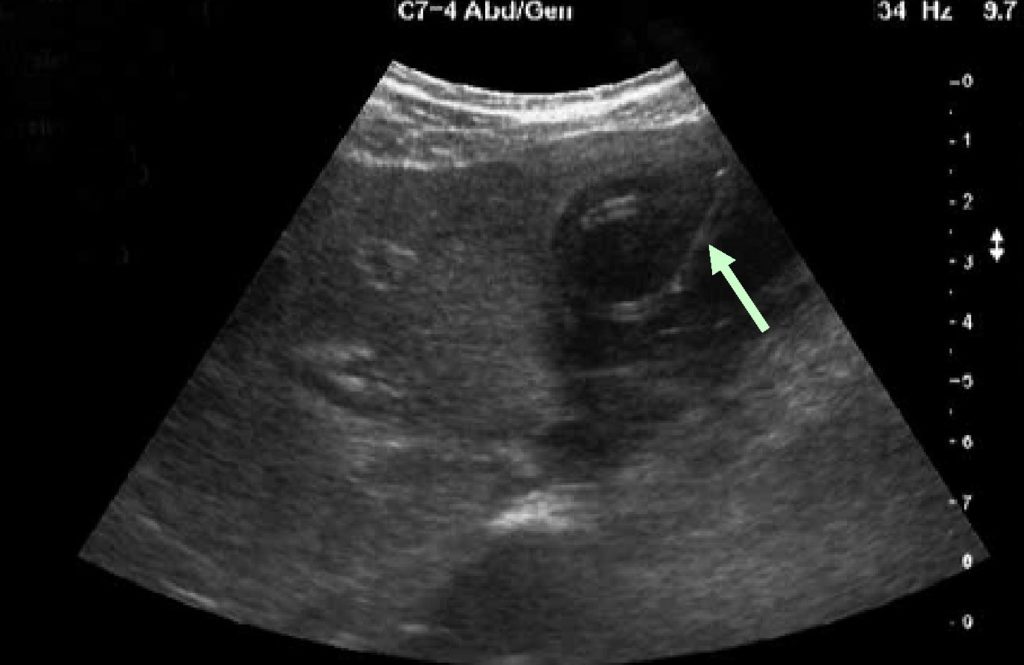

Эхографическое сканирование позволяет определить размеры поджелудочной железы и ее структуру. Оно также используется для дифференциальной диагностики с опухолями, калькулезными холециститами, хроническими энтеритами и другими серьезными заболеваниями ЖКТ.

Ультразвуковое исследование показывает, что плотность поджелудочной железы увеличена, но значительной разницы в размерах не наблюдается. Помимо этого, при диагностике проводятся также анализы кала на непереваренную пищу, сбор анамнеза, пальпация живота и общий визуальный осмотр.